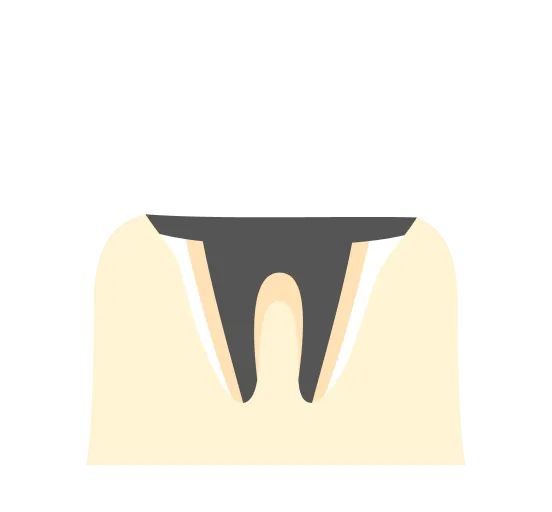

進行度と治療方法